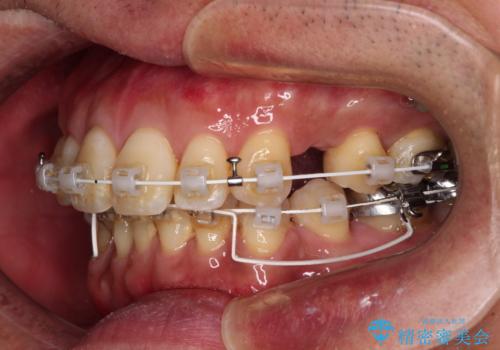

- 審美装置

- 口元の突出感を気にして来院された患者様です。

強い咬合力と上顎前歯の傾斜により前歯が突出し、唇が閉じにくい状況であったため、上下左右の第一小臼歯4本を抜歯し、ワイヤー装置にて矯正治療を行うこととしました。

非常に咬合力が強いため、抜歯したスペースが閉じるのか不安でしたが、順調に歯が移動し、予定よりも早く治療を終えることができました。